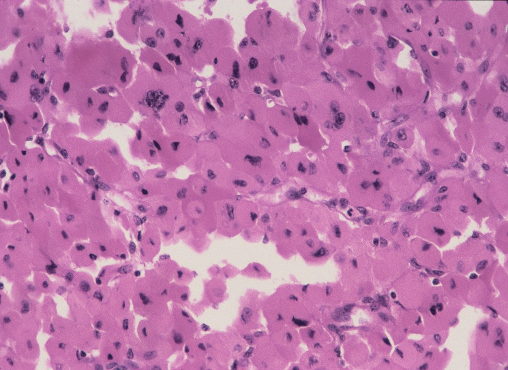

Ans to previous : (October 2024)

Renal Cell carcinoma -clear cell type.

The 2 factors at gross with a poor prognosis are the size of tumour ie 12 cms and the presence of necrosis. Presence of necrosis is considered an independent prognostic factor. The grade of tumour in the figs shown was given as 2 and stage was T2.

Grading of RCC :

A modified grading system for renal cell carcinoma (RCC) that incorporates tumor necrosis is as follows:

• Grade 1: ISUP grade 1 and non-necrotic ISUP grade 2

• Grade 2: Necrotic ISUP grade 2 and non-necrotic ISUP grade 3

• Grade 3: Necrotic ISUP grade 3 and non-necrotic nonsarcomatoid/rhabdoid ISUP grade 4

• Grade 4: Necrotic ISUP grade 4 and sarcomoatid/rhabdoid features

Tumor necrosis is an independent predictor of adverse outcome in RCC. This modified grading system outperforms the ISUP grading system and shows significant differences in survival between each grade.